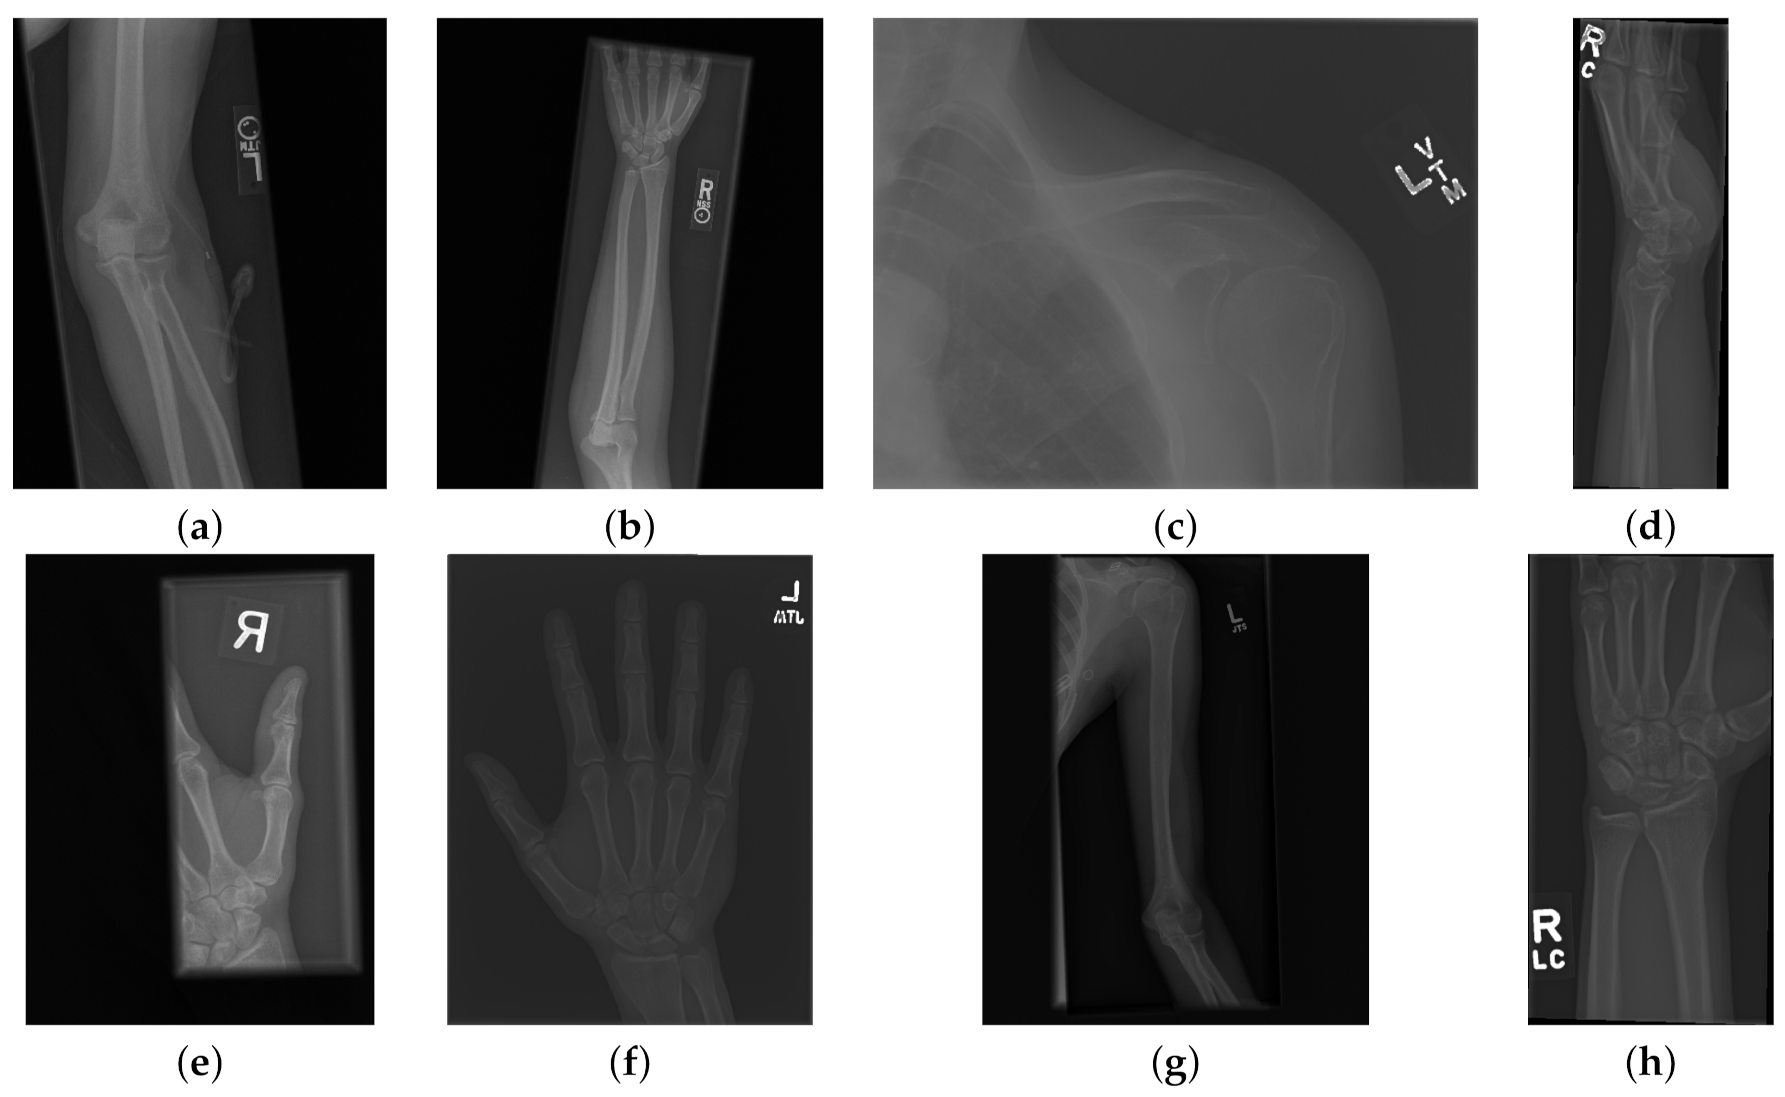

The data used to compare the 11 CNNs was obtained from the public dataset MUsculoskeletal RAdiographs (MURA) from a competition organised by researchers from Stanford University [59]. The dataset has been manually labelled by board-certified radiologists between 2001 and 2012. The studies (n = 14,656) are divided into training (n = 13,457), and validation (n = 1199). Furthermore, the studies have been allocated in groups called abnormal (i.e., those radiographs that contained fractured bones, foreign bodies such as implants, wires or screws, etc.) ( n = 5715 ) or normal ( n = 8941 ). Representative normal cases are illustrated in Figure 1 and abnormal cases in Figure 2. The distribution per anatomical region is shown in Table 1. In this paper, the subset of the wrists was selected. The cases of normal and abnormal wrist radiographs is presented in Table 2. Notice that these were subdivided into four studies.

Figure 2. Eight examples of radiographs with abnormalities (considered positive) of the Musculoskeletal Radiographs (MURA) dataset [59]. (a) Elbow, (b) Forearm, (c) Shoulder, (d) Wrist (lateral view), (d) Lateral view of Wrist, (e) Finger, (f) Hand, (g) Humerus, (h) Wrist. As for the cases without abnormalities, it should be noted the variability of the images and in addition the abnormalities themselves. There are cases of metallic implants some of which are smaller (a) than others (b), as well as fractures.